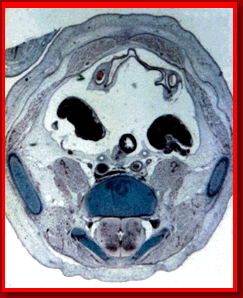

CORTE TRANSVERSAL DEL ABDOMEN FETAL

Médula Espinal

Vertebra Lumbar

Ilion

Vejiga

Arteria Umbilical

Gónadas

Cavidad Peritoneal

Intestino

Arterias Iliacas